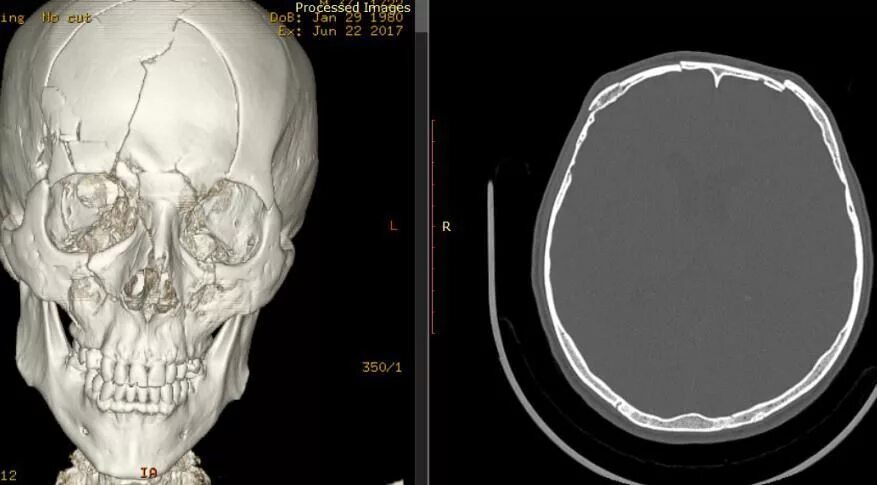

Оскольчатый перелом черепа